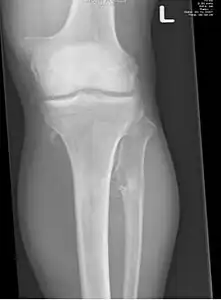

The diagnosis of HMO is based upon establishing an accurate correlation between the above-mentioned clinical features and the characteristic radiographic features. Family history can provide an important clue to the diagnosis. This is supplemented by testing for the two genes in which pathogenic variants are known to cause HMO namely EXT1 and EXT2. A combination of sequence analysis and deletion analysis of the entire coding regions of both EXT1 and EXT2 detects pathogenic variants in 70–95% of affected individuals.[3][4] The hallmark of radiographic diagnosis is the presence of osteochondromas at the metaphyseal ends of long bones in which the cortex and medulla of the osteochondroma represent a continuous extension of the host bone. This is readily demonstrable in radiographs of the knees.[3][1]

- multiple osteochondromas around the knee